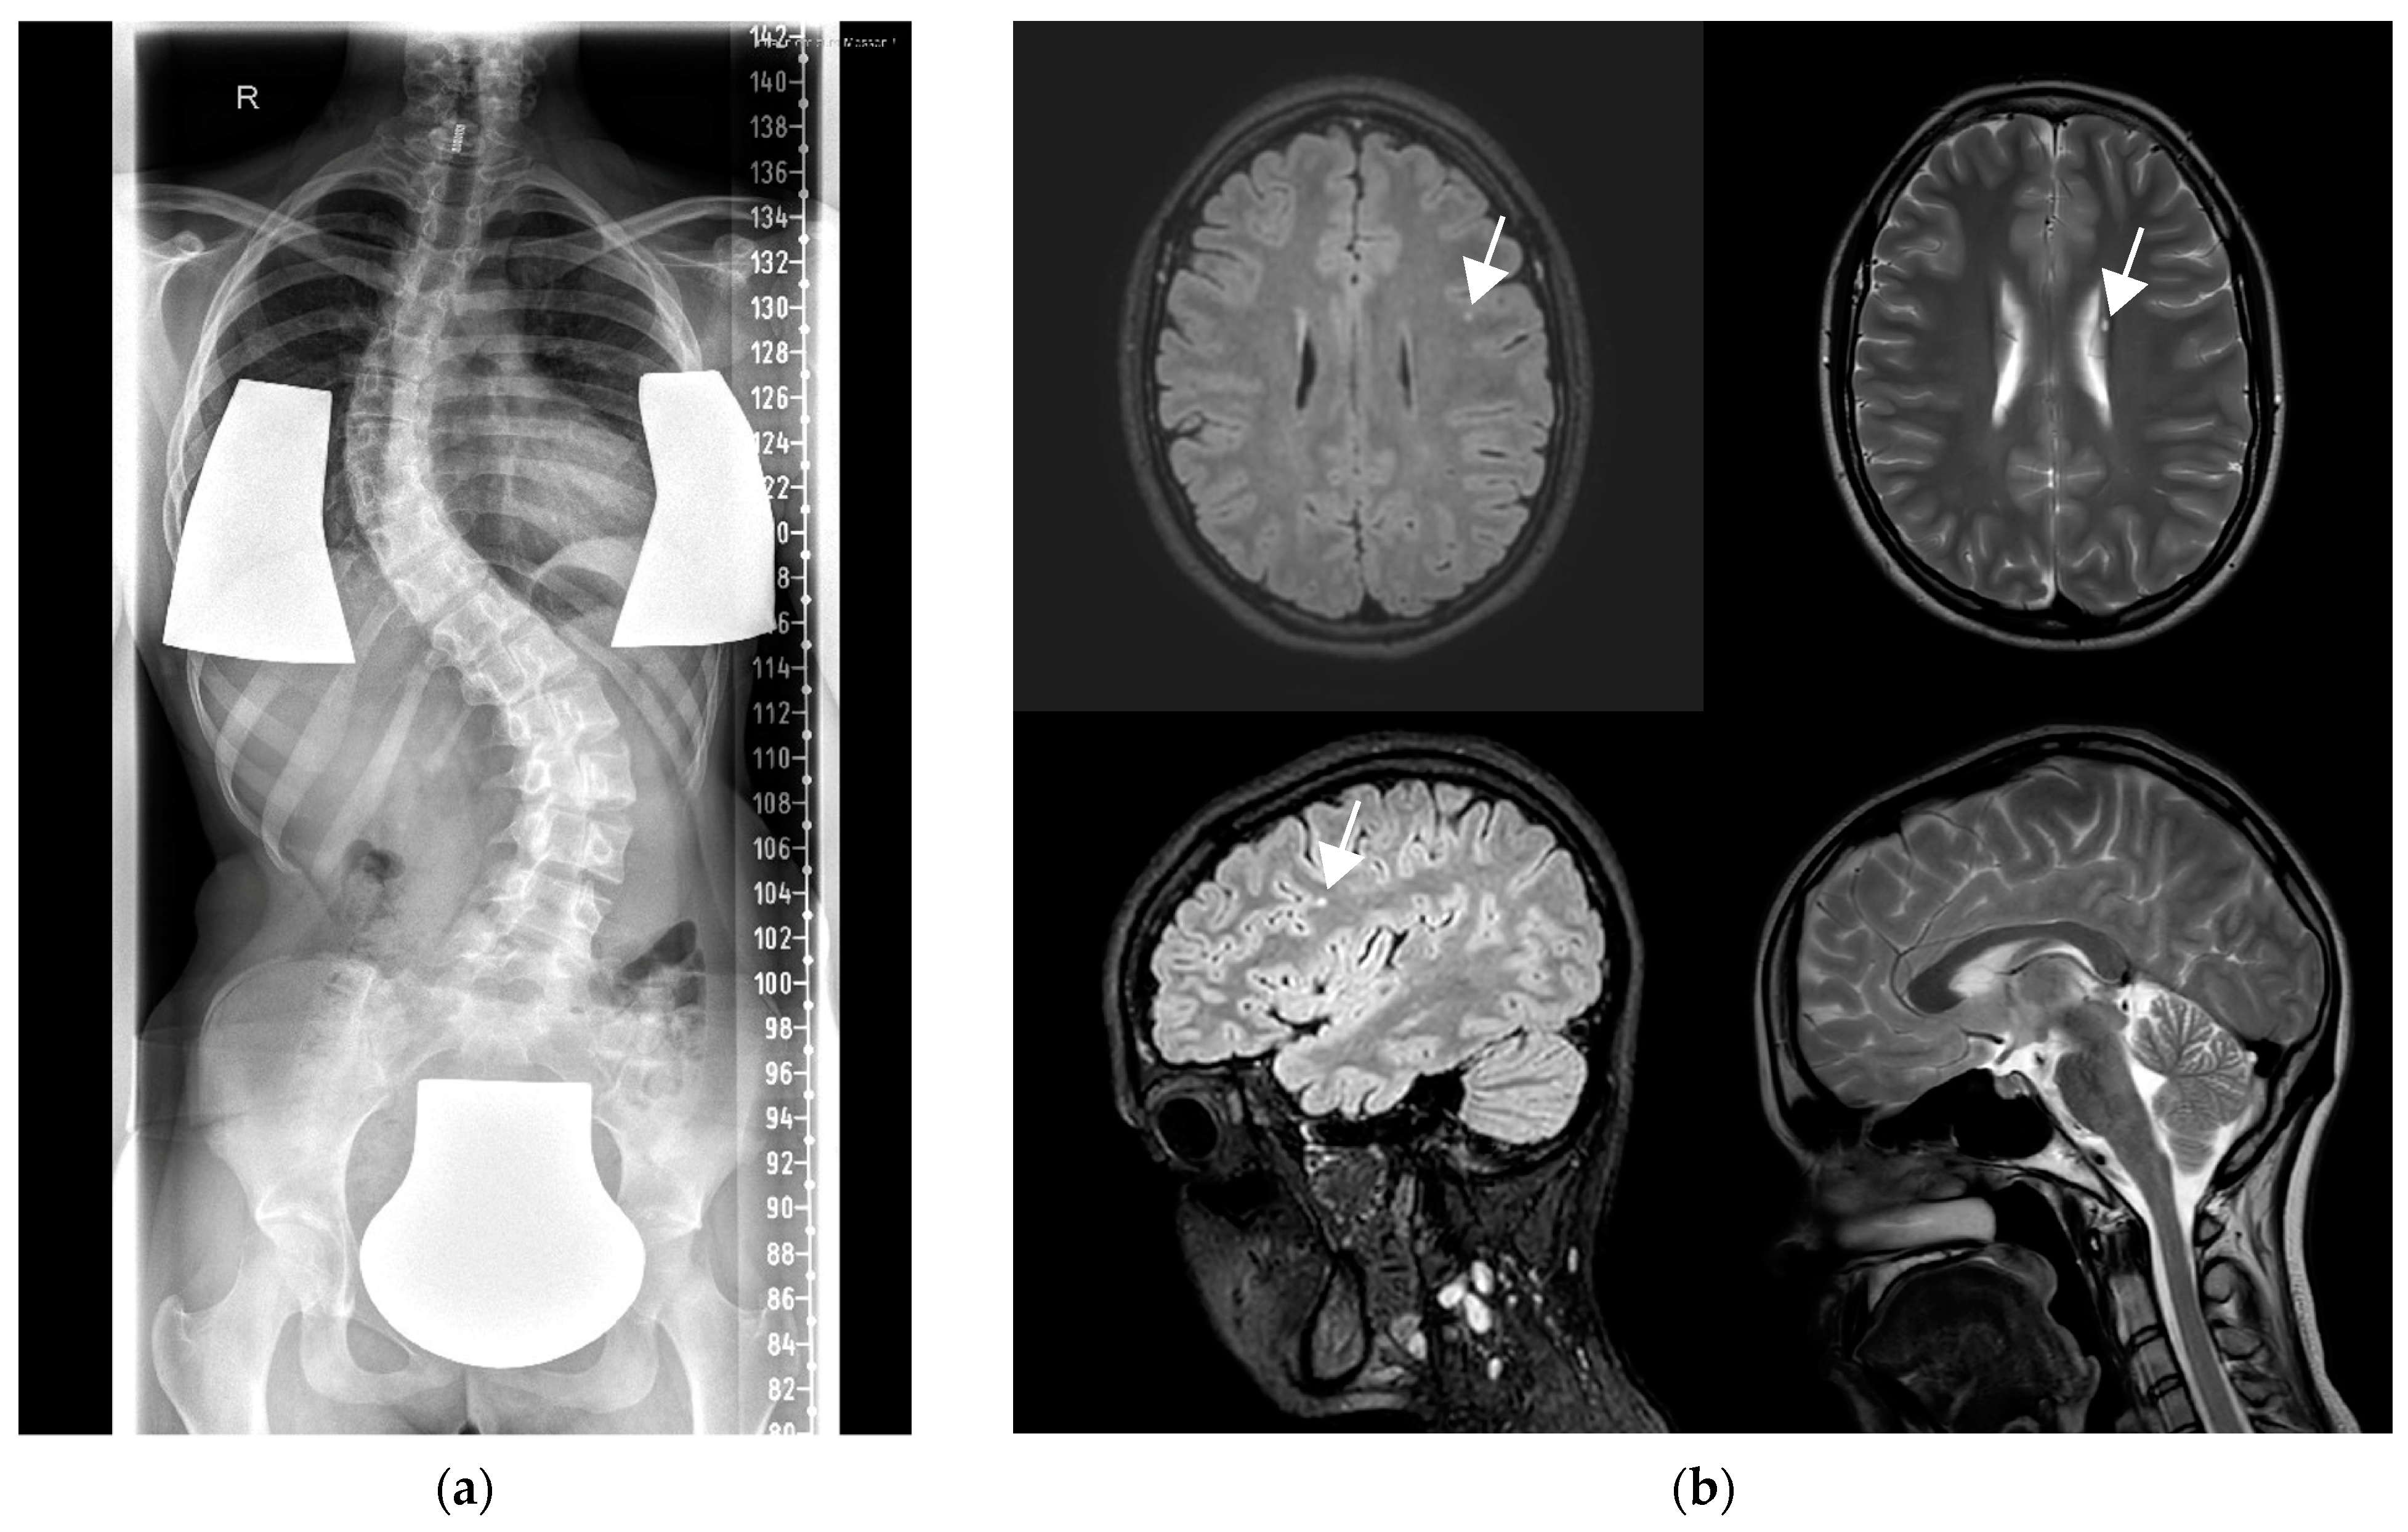

| This study | #43 (15 y) | comp het, c.364G>A (p.Glu122Lys), c.336+1G>A (p.?) | + (12 y) | + (8 y) | + (2 y) | Mild ID |

| #44 (21 y) | hom, c.430G>T (p.Gly144Trp) | + (16 y) | + (13 y) | + (GTCS 12y on urinary tract infection) | Gradual progression of movement disorders into dystonia on recurrent viral infections |